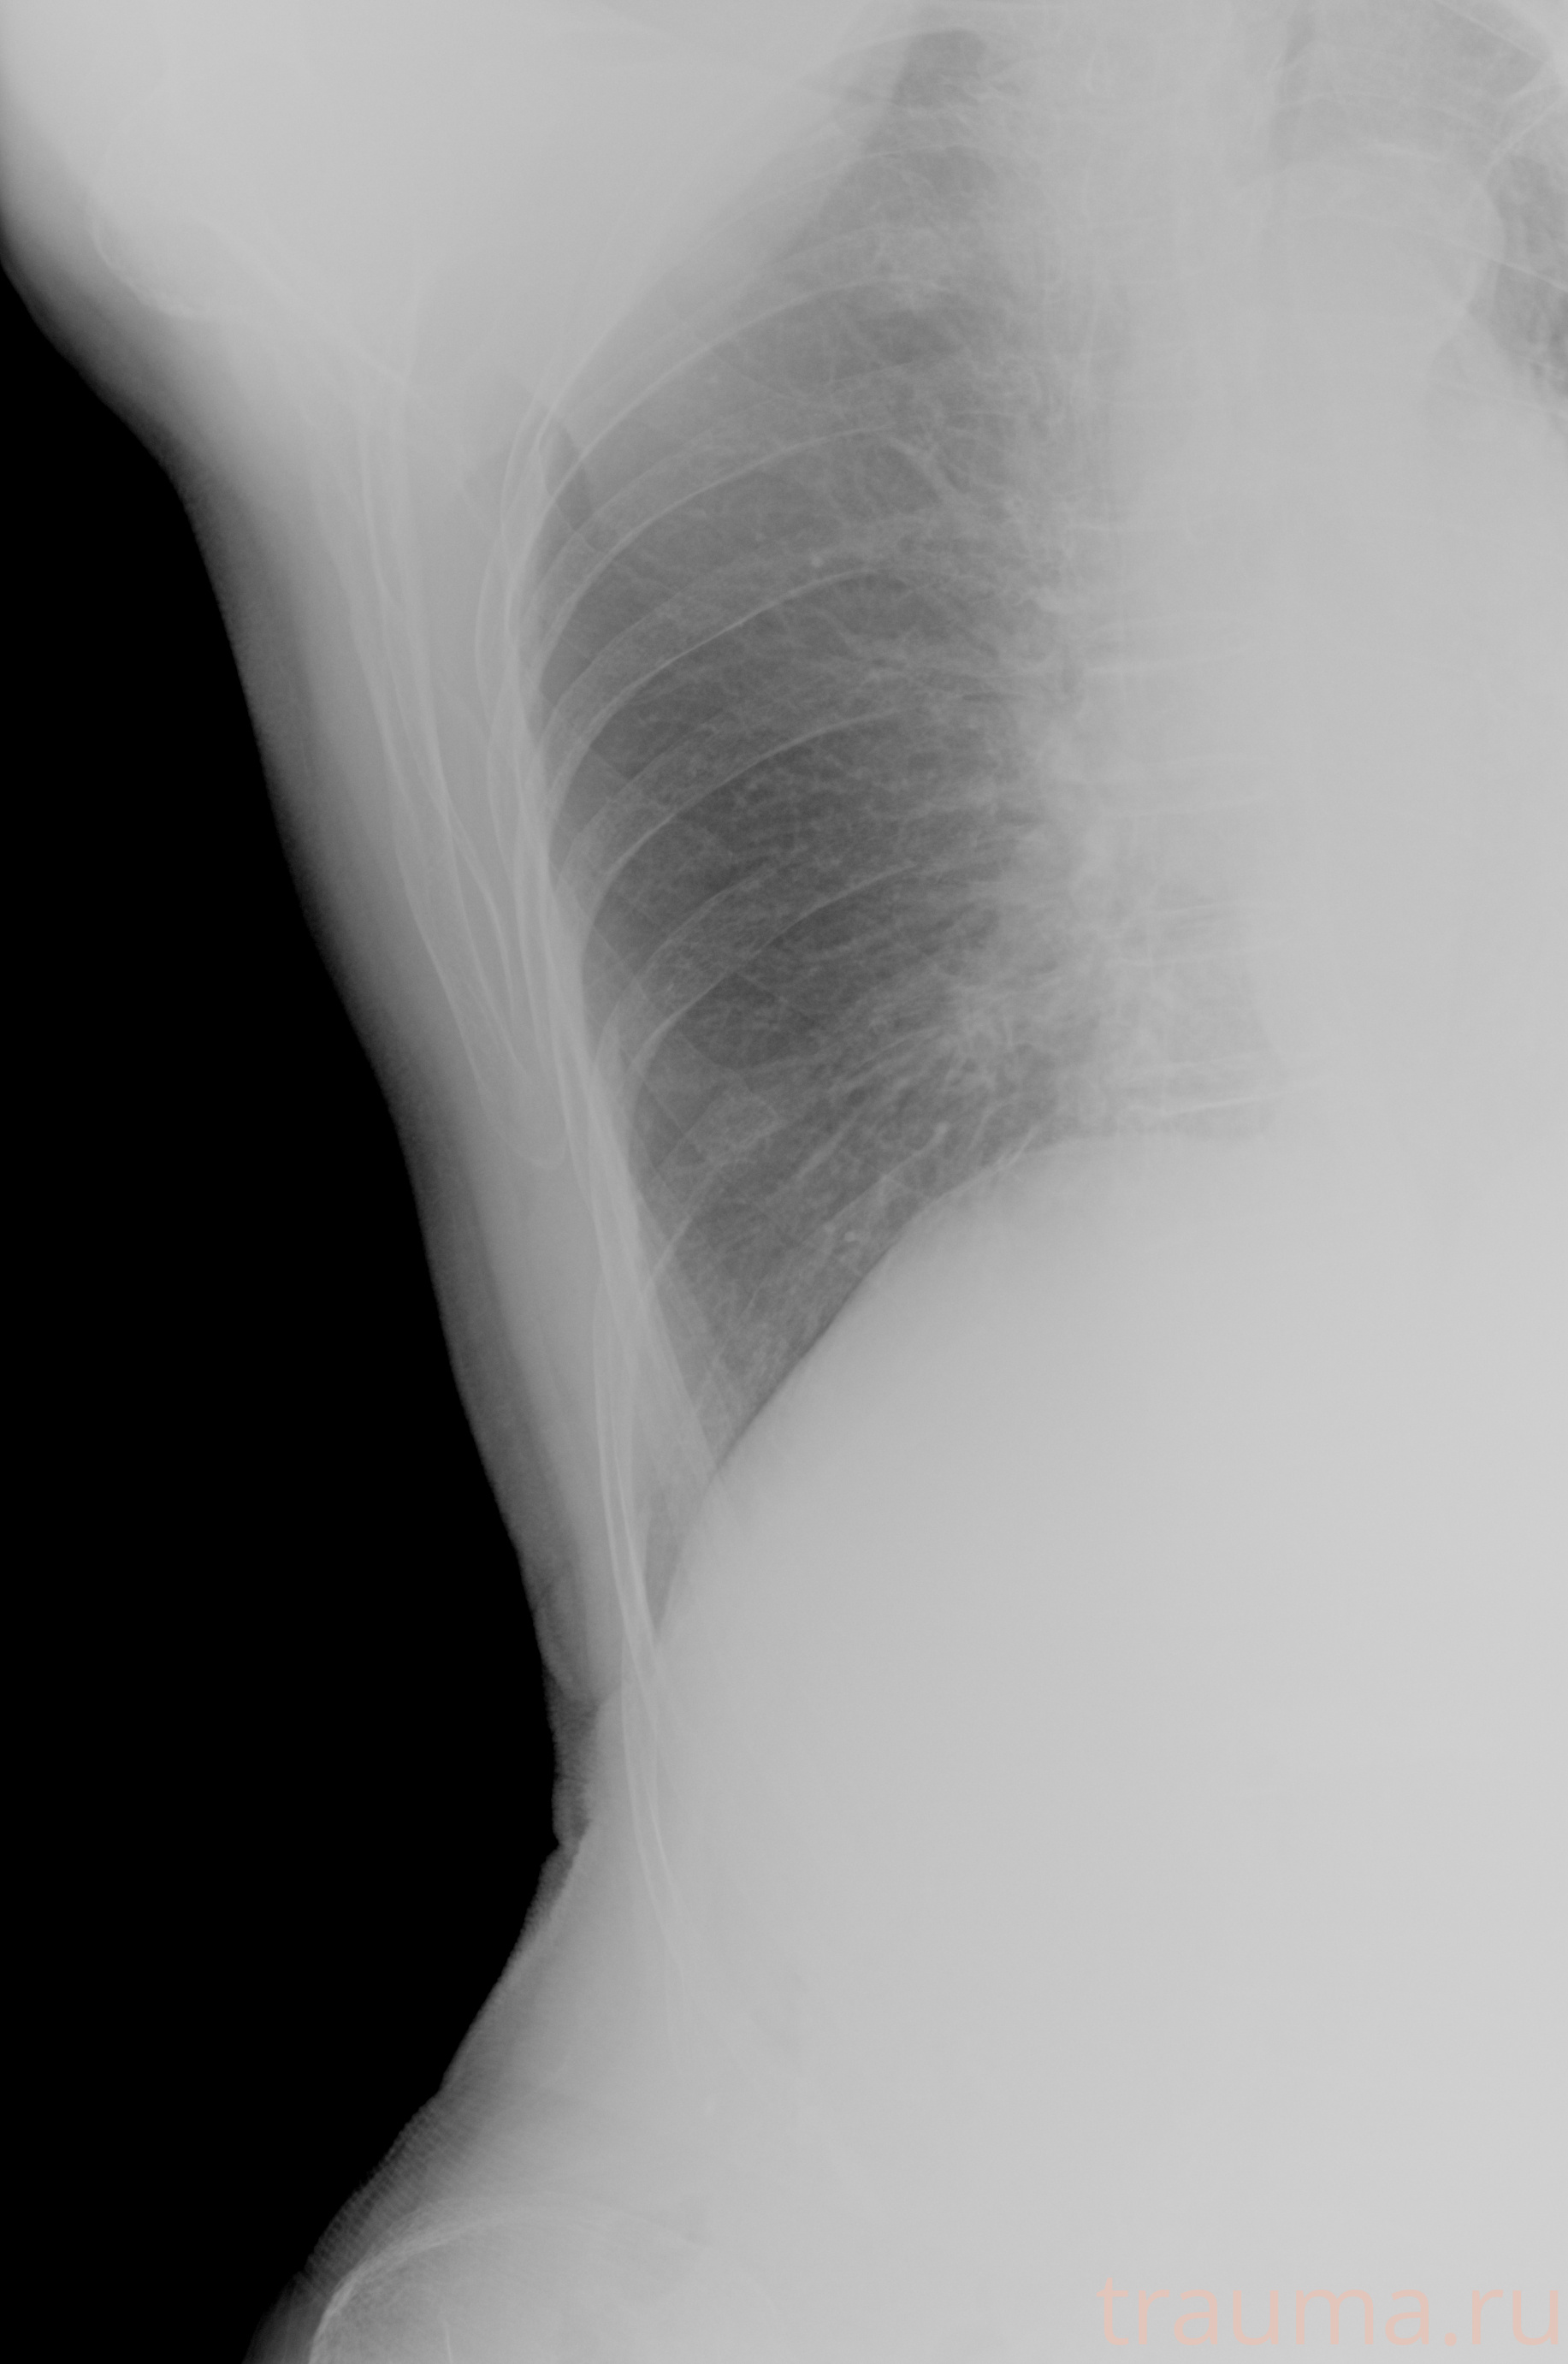

Рентгенограммы

Рентген на дому: по вашему адресу приезжает врач-рентгенолог, травматолог-ортопед с мобильным рентгеновским аппаратом, проводит диагностику травмы или заболевания, делает необходимые рентгенограммы, дает рекомендации по дальнейшему лечению. Получить качественные снимки в домашних условиях возможно благодаря уникальной методике, разработанной МосРентген Центром для института  Склифосовского

при переломе шейки бедра и пневмонии от компании МосРентген Центр - партнера Института имени Склифосовского